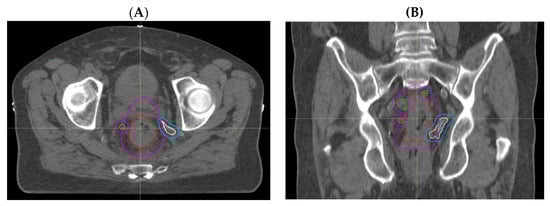

3.1.2. Comparison of Volumes Using Adjusted MRI Reporting with Historical Radiotherapy Volumes